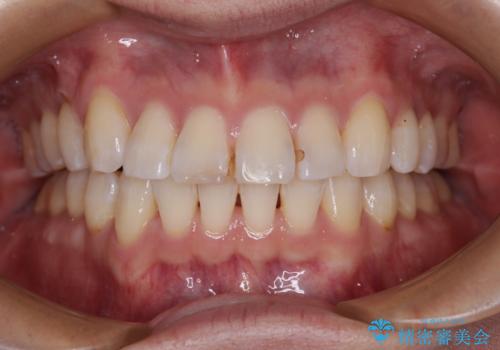

動きにくい歯はやはり動きにくく、咬み合わせ改善に時間を要しましたが、患者様には大変満足していただけました。